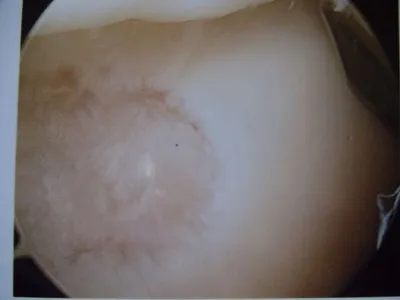

Pic of one of the nodules inside the ankle joint.